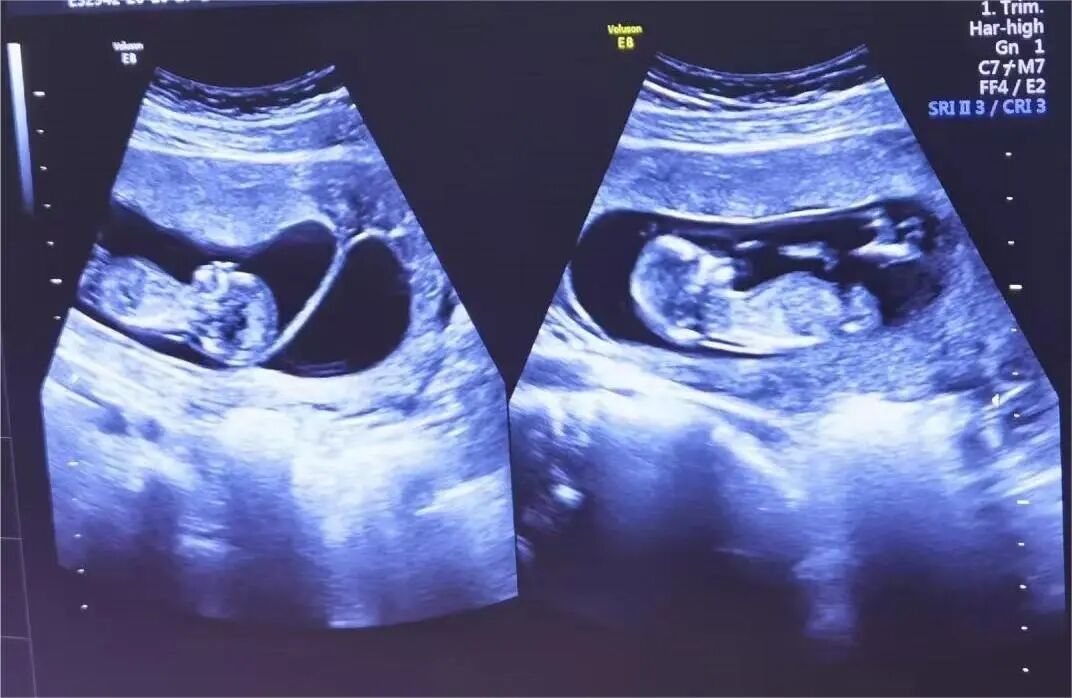

多年来,贵州航天医院各科室紧跟医学前沿,不断强技术、补短板,大力开展新技术、新项目,完成了许多高精尖、高难度、本地区“首例”的技术,填补了医院医疗技术空白,满足了群众日益增长的医疗需求。 复杂性双胎超声监护耗时耗力,技术难度大,风险高,为填补本地区复杂性双胎的超声监护技术空白,我院超声科在遵义市率先开展了此项技术,有效满足了双胎孕妇产检需求,保障了双胎新生儿的平安健康。 本期,我们将为大家带来超声科特色技术——复杂性双胎的超声监护。 案例分享 案例一 28岁的孕妇,自然受孕,怀有单绒毛膜双羊膜囊双胎(MCDA),在我院定期产检的过程中,孕32周超声检查发现两个胎儿的大脑中动脉血流流速(MCA-PSV)相差>0.7倍数的正常值(MoM),高度怀疑发生了双胎贫血红细胞增多序列征(TAPS)。为进一步明确诊断,产科立即组织超声科、手术室、新生儿科等科室进行多学科会诊(MDT),诊断为:双胎贫血红细胞增多序列征(TAPS),在征得孕妇及其家属的同意后,决定提前分娩,及时保障了两名胎儿的生命和健康。 双胎大脑中动脉血流 双胎贫血红细胞增多序列征(TAPS) 案例二 一名26岁的孕妇,是完全双角子宫,且为左侧子宫妊娠,怀有单绒毛膜双羊膜囊双胎(MCDA),一直在我院规律产检,孕16周时,超声检查发现双胎生长不一致,体重相差超过25%,考虑子宫畸形合并早发选择性胎儿宫内生长受限。孕妇在咨询相关上级医院专家后,得到减胎的建议,又前来我院咨询,在我院超声科和产科的合作下,查阅了大量文献、认真评估检查报告后,建议孕妇继续双胎妊娠。在规律、严密的超声监护下,双胎除体重差异外未出现严重胎儿并发症,在34周进行了分娩,截至目前,新生儿生长发育均正常。 胎儿生长曲线及子宫畸形三维重建 出生时体重差异 十月龄时 案例三 一名30岁的孕妇,自然受孕,怀有单绒毛膜双羊膜囊双胎(MCDA),在孕22周时超声检查发现双胎发生了选择性胎儿宫内生长受限,遂转诊到上级医院拟行胎儿镜治疗,但在行治疗的前一天,较小的胎儿在宫内发生死亡,在充分与孕妇及家属沟通后,要求继续妊娠,在定期规范的产检下,严密监测胎儿生长发育及胎儿颅脑MRI影像,最终在孕37周时通过剖宫产分娩,目前新生儿生长发育情况良好。 双胎之一胎死宫内(右图) 贵州航天医院自2021年开展复杂性双胎的超声监护以来,已服务大量双胎孕妇,集齐了所有单绒毛膜双羊膜囊双胎(MCDA)并发症病例,由经验丰富的超声医师进行此项检查,产科专业团队进行双胎的规范化监护和分娩,并与重庆医科大学附属第一医院建立了转诊通道,能够及时获得该院专家的指导和支持,为广大孕产妇提供优质、全面的医疗保障。 点击跳转贵州航天医院便民服务电话 什么是复杂性双胎的超声监护 “双胎”被称为产科之王,单绒毛膜双胎则为王中王,主要是因为单绒毛膜双羊膜囊双胎(MCDA)两胎儿共用一个胎盘,胎盘中存在血管吻合。 双胎妊娠的产前筛查及诊断主要依靠超声,相对于单胎妊娠,双胎妊娠并不是单胎检查的重复,双胎妊娠尤其是复杂性双胎的超声诊断更为重要的是关注双胎间循环的关联,双胎间生理及病理改变的相互影响,双胎间血流动力学监测及双胎间差异比较。 超声如何诊断 复杂性双胎并发症 在孕14周以前,超声要明确双胎的绒毛膜性:是单绒毛膜(MC)还是双绒毛膜(DC);孕10周前,可以通过孕囊的个数确定绒毛膜性;孕11周—14周,可以通过胎儿的性别、双胎之间隔膜的厚度、双胎儿分隔膜处胎盘的形态等来区分绒毛膜性。 双绒毛膜双胎的管理和单胎差不多,基本不需要增加超声检查的频次。单绒毛膜的管理相对谨慎,按照国际国内指南规范,单绒毛膜双胎自第16周起,每两周对双胎儿进行生长发育评估及血流检查。 复杂性双胎的超声监护,对超声医生技术要求较高,孕早期需对双胎的绒毛膜性进行精确判断;产科医生根据绒毛膜性制定孕期的产检计划;超声医生掌握胎儿宫内情况,及时与产科医生沟通,精确了解胎儿宫内安危后制定合适的治疗方案,给出适当的终止妊娠时机;复杂性双胎一般都面临早产的风险,所以新生儿团队的专业保障不可或缺,降低新生儿出生后的并发症及提高新生儿生活质量。复杂性双胎的较好妊娠结局,是通过孕期超声科、产科紧密合作,及新生儿出生后新生儿科管理多学科团队合作所获得的。 贵州航天医院超声科专家团队 吴艳辉 超声科 学科带头人 主任医师 专业擅长:从事超声诊断工作约30年,对心血管、小器官超声、超声引导下介入等具有丰富的临床经验。 骆科美 超声科 副主任医师 专业擅长:从事超声诊断工作33年,对胎儿心脏及颅脑、妇产超声诊断、盆底超声等诊断具有丰富的临床经验。 胡大海 超声科 副主任医师 专业擅长:从事超声工作17年,对心血管、外周血管、浅表器官超声诊断等具有丰富的临床经验。 刘 敏 超声科 副主任医师 专业擅长:从事超声诊断工作20余年,对妇产科超声、心脏血管超声诊断具有丰富的临床经验。 贵州航天医院超声科简介 贵州航天医院超声科配备多种超声检查设备(飞利浦彩超(IU-22、IU-Elite、HD11、Q5、Q7),迈瑞超声I9、DC-6、DC-8、GE-E8及床旁机,彩色超声诊断仪等),设有心血管诊室、妇产科诊室、腹部诊室、绿色通道、浅表小器官等检查室。 • ✦ 专科特色 ✦ • 四肢血管超声检查、双胎产前筛查及超声监护、超声造影检查技术、介入超声临床应用、经颅脑实质超声辅助筛查诊断帕金森病、女性性早熟超声诊断、盆底超声检查等。 NT超声检查 超声介入引导 肝脏超声造影 甲状腺造影 颅脑超声帕金森辅助检查 乳腺超声造影 上肢动静脉造瘘超声检查 双胎超声筛查 下肢血管超声检查 右心造影 • ✦ 诊疗范围 ✦ • 科室业务覆盖腹部、泌尿、妇科、产科(常规、NT筛查、III级筛查超声检查及高危妊娠监护)、成人心脏、外周血管、浅表器官(包含甲状腺、乳腺、阴囊、眼睛等)、颅脑(小儿颅脑、成人颅脑)、小儿肺超、造影、盆底、腹直肌、肌骨神经等检查及各种介入引导。